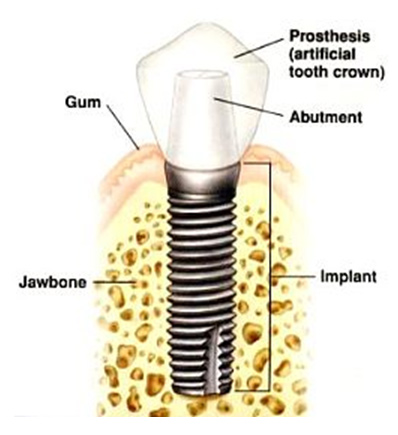

Implants are alternatives to complex restorative treatment on your natural tooth such as conventional bridges, and dentures. Constructed of Titanium an implant is placed into your jaw bone. Implants are safe, non-toxic, and biocompatible. Your bone will grow around the implant and osseo-integrate to the fixture. First tried over 30 years ago, dental implants have evolved to provide a treatment option with 95% success rate over 10 years. Now considered the Number 1 option to replace a missing tooth, implant based treatment is the future of replacing gaps.

Placement of a Dental Implant